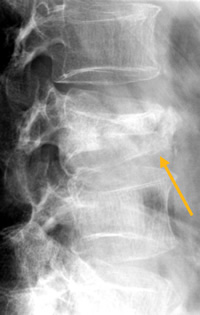

Beispiel eines "konsolidierten" WK-Einbruchs

So entsteht durch einen WK-Einbruch eine Kyphose. Unabhängig ob M. Scheuermann, Unfall, oder Osteoporose oder mehrere Ursachen gleichzeitig!